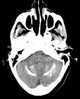

Primary familial brain calcification (PFBC), also known as familial idiopathic basal ganglia calcification (FIBGC) and Fahr's disease, is a rare, genetically dominant, inherited neurological disorder characterized by abnormal deposits of calcium in areas of the brain that control movement. Through the use of CT scans, calcifications are seen primarily in the basal ganglia and in other areas such as the cerebral cortex. [Source: Wikipedia ]